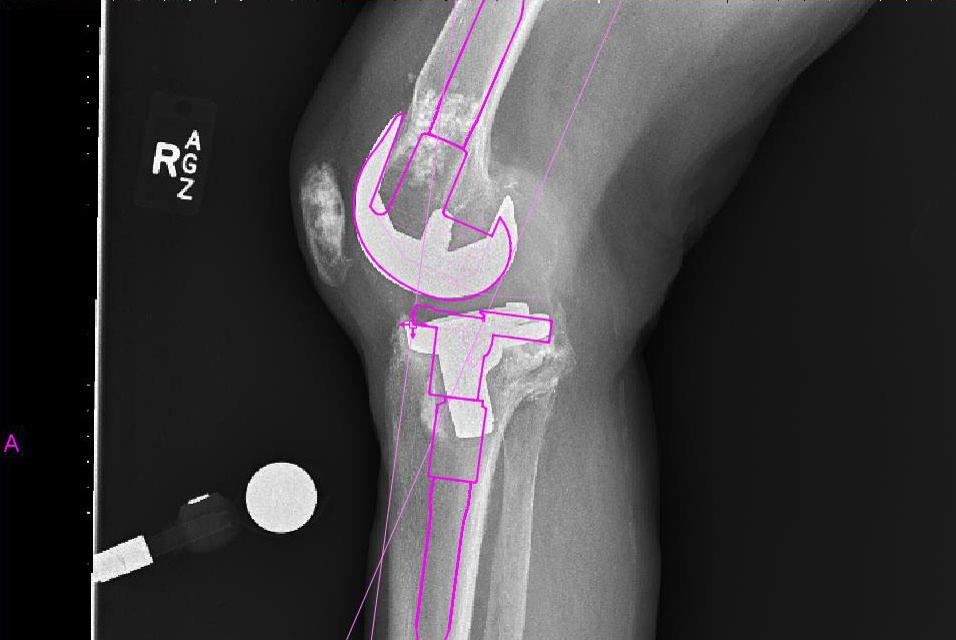

Templating on the lateral view permits assessment of the proposed joint line. Augments can readily be added to the distal femur or tibia if the templated polyethylene size is too large, or the joint line is too high or low, based on bony landmarks.

The preoperative planning software allows the width of the femur and tibia to be assessed for proper component sizing, which is important as size is the primary focus, rather than angles. Intramedullary guides are used to restore the mechanical axis. Also key with revisions is identifying where the articular surfaces of the revision components would lie, in relation to the shaft. Further, it is helpful to preoperatively determine the offset of the tibial component (more than that of the femoral component), as this can help intra-operatively reduce the need for trialing of various tibial stems.

The tibial AP axis indicates that an offset tibial stem will be needed.